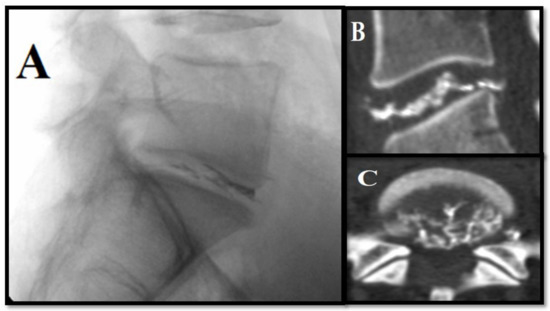

- Marcia, S.; Bellini, M.; Hirsch, J.A.; Chandra, R.V.; Piras, E.; Marras, M.; Sanna, A.M.; Saba, L. Efficacy of an ethyl alcohol gel in symptomatic disc herniation. Eur. J. Radiol. 2018, 109, 101–107. [Google Scholar] [CrossRef]

- Houra, K.; Perovic, D.; Rados, I.; Kvesic, D. Radiopaque gelified ethanol application in lumbar intervertebral soft disc herniations: Croatian multicentric study. Pain Med. 2018, 19, 1550–1558. [Google Scholar] [CrossRef]

- Stagni, S.; De Santis, F.; Cirillo, L.; Dall’Olio, M.; Princiotta, C.; Simonetti, L.; Stafa, A.; Leonardi, M. A minimally invasive treatment for lumbar disc herniation: DiscoGel chemonucleolysis in patients unresponsive to chemonucleolysis with oxygen-ozone. Interv. Neuroradiol. 2012, 18, 97–104. [Google Scholar] [CrossRef]

- Léglise, A.; Lombard, J.; Moufid, A. DiscoGel in patients with discallumbosciatica: Retrospective results in 25 consecutive patients. Orthop. Traumatol. Surg Res. 2015, 101, 623–626. [Google Scholar] [CrossRef][Green Version]

- De Sèze, M.; Saliba, L.; Mazaux, J.M. Percutaneous treatment of sciatica caused by a herniated disc: An exploratory study on the use of gaseous discography and Discogel in 79 patients. Ann. Phys. Rehabil. Med. 2013, 56, 143–154. [Google Scholar] [CrossRef][Green Version]